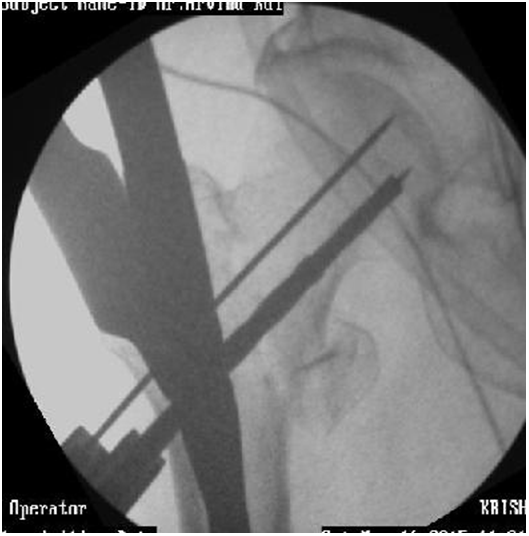

Use of curved femur finder device, retractor push, cannulated curved awl to pass the guide wire in correct direction (Figures 14-17).

Figure 14 Guide wire in canal deviating medially.

Figure 15 Redirection by Retractor push, Femur finder, Cannulated awl.4

Figure 16 Guide wire going medially sometimes can exits out through fracture and damage neurovascular structures.

Figure 17 Redirected Guide wire in canal.